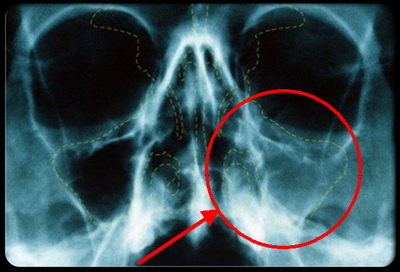

Рентгенограмма приносовых синусов.

Расшифровывая снимок пациента с синуситом, можно сразу же провести более детальную дифференциальную диагностику, согласно его локализации и распространенности.

Рентгенологическая классификация синуситов:

- Гайморит – локализация в гайморовых (верхнечелюстных) пазухах.

- Фронтит – патология лобных синусов.

Сфеноидит – воспаление пазухи клинообразной кости.

- Этмоидит – воспалительный процесс в синусах сосцевидного отростка.

- Моносинусит – процесс протекает только в одном синусе.

- Полисинусит – в воспаление втянуты несколько пазух разных костей.

- Гемисинусит – поражение всех пазух с одной из сторон (правой или левой).

- Пансинусит – одновременное втягивание в воспалительный процесс всех околоносовых пазух.